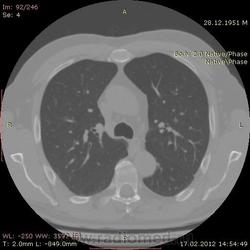

КТ.

В феврале 2012 года при очередном флюрографическом обследовании были обнаружены изменения в лёгких. По собственной инициативе было сделано КТ лёгких.